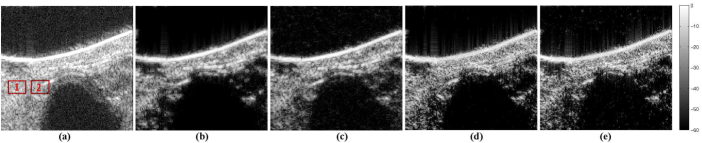

III-B Results on simulated ultrasound images

In this section, we compared the compressive deconvolution results with our method to those obtained with a sequential approach. The latter recovers in a first step the blurred US image from the CS measurements and reconstructs in a second step the TRF by deconvolution.

Two ultrasound data sets were generated, as shown in Figures 2 and 3. They were obtained by 2D convolution between spatially invariant PSFs and the TRFs. For the first simulated image, the same PSF as in the previous section was simulated and the TRF corresponds to a simple medium representing a round hypoechoic inclusion into a homogeneous medium. The scatterer amplitudes were random variables distributed according to a GGD with the shape parameter set to 1. The second data set is one of the examples proposed by the Field II simulator [46], mimicking a kidney tissue. The PSF was also generated with Field II corresponding to a 4 MHz central frequency and an axial sampling frequency of 40 MHz. It corresponds to a focalized emission (the PSF was measured at the focal point) with a simulated linear probe containing 128 elements. The shape parameter of the GGD used to generate the scatterer amplitudes was set to 1.51.51.5 and the number of scatterers was considered sufficiently large (106superscript10610^{6}) to ensure fully developped speckle. In both experiments, the compressed measurements were obtained by projecting the RF images on SRM, aiming at reducing the amount of data available.

Refer to caption

Figure 2: Simulated US image and its compressive deconvolution results for a CS ratio of 0.4 and a SNR of 40 dB. (a) Original tissue reflectivity function, (b) Simulated US image, (c) Results using the sequential method, (d, e, f) Results with the proposed method for p𝑝p equal to 1.5, 1.3 and 1 respectively.

Figure 3: Simulated kidney image and its compressive deconvolution results for a CS ratio of 0.2 and a SNR of 40dB. (a) Original tissue reflectivity function, (b) Simulated US image, (c) Results using the sequential method, (d, e, f) Results with the proposed method for p𝑝p equal to 1.5, 1.3 and 1 respectively.

With the sequential approach, YALL1 [42] was used to process the CS reconstruction following the minimization in eq. (3). The deconvolution step was processed using the Forward-Backward Splitting method [48, 49]. Both the CS reconstruction and the deconvolution procedures were performed with the same priors as the proposed compressive deconvolution approach.

The algorithm stops when the convergence criterion 𝒙k𝒙k1/𝒙k1<1e3normsuperscript𝒙𝑘superscript𝒙𝑘1normsuperscript𝒙𝑘11superscript𝑒3\parallel\bm{x}^{k}-\bm{x}^{k-1}\parallel/\parallel\bm{x}^{k-1}\parallel<1e^{-3} is satisfied. In order to highlight the influence of these hyperparameters on the reconstruction results, we consider the simulated US image in Fig. 2. The PSNR values obtained while varying the values of these hyperparameters are shown in Fig. 4. From Fig. 4, one can observe that the best results are obtained for small values of μ𝜇\mu, corresponding to an important weight given to the data attachment term. The best value of α𝛼\alpha is the one providing the best compromise between the two prior terms considered in eq. (6), promoting minimal 1subscript1\ell_{1}-norm of H𝒙𝐻𝒙H\bm{x} in the wavelet domain and GGD statistics for 𝒙𝒙\bm{x}. The choice of β𝛽\beta and γ𝛾\gamma parameters, used in the augmented Lagrangian function and in the approximation of the psubscript𝑝\ell_{p}-norm proximal operator, have an important impact on the algorithm convergence. Moreover, one may observe that for a given range of values, the choice of γ𝛾\gamma has less impact on the quality of the results than the other three hyperparameters. Despite different optimal values for each CS ratio, in the results presented through the paper, we considered their values fixed for all the CS ratios. The hyperparameters with our approach were set to {μ,α,β,γ}={105,2×101,1,102}𝜇𝛼𝛽𝛾superscript1052superscript1011superscript102\{\mu,\alpha,\beta,\gamma\}=\{10^{-5},2\times 10^{-1},1,10^{-2}\} for the round cyst image and {μ,α,β,γ}={105,2×101,1×103,104}𝜇𝛼𝛽𝛾superscript1052superscript1011superscript103superscript104\{\mu,\alpha,\beta,\gamma\}=\{10^{-5},2\times 10^{-1},1\times 10^{3},10^{-4}\} for the simulated kidney image.

The quantitative results in Table II show that the proposed method outperforms the sequential approach, for all the CS ratios and values of p𝑝p considered. They confirm the visual impression given by Figures 2 and 3. We should remark that for the first simulated data set, the l1subscript𝑙1l_{1}-norm gives the best result. This may be explained by the simple geometry of the simulated TRF, namely its sparse appearance. The second data set, more realistic and more representative of experimental situations, shows the interest of using different values of p𝑝p. It confirms the generality interest of the proposed method, namely its flexibility in the choice of TRF priors.